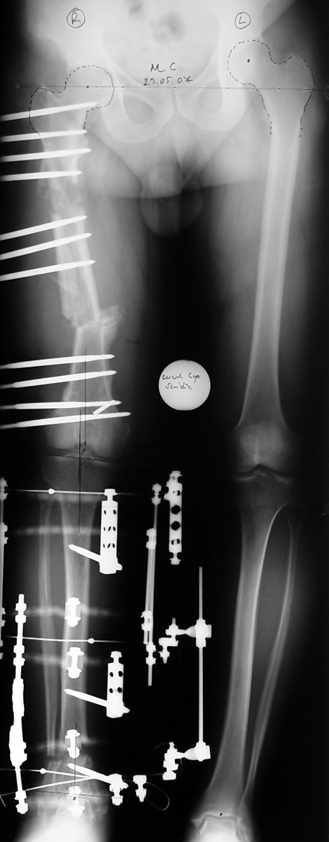

Case 2